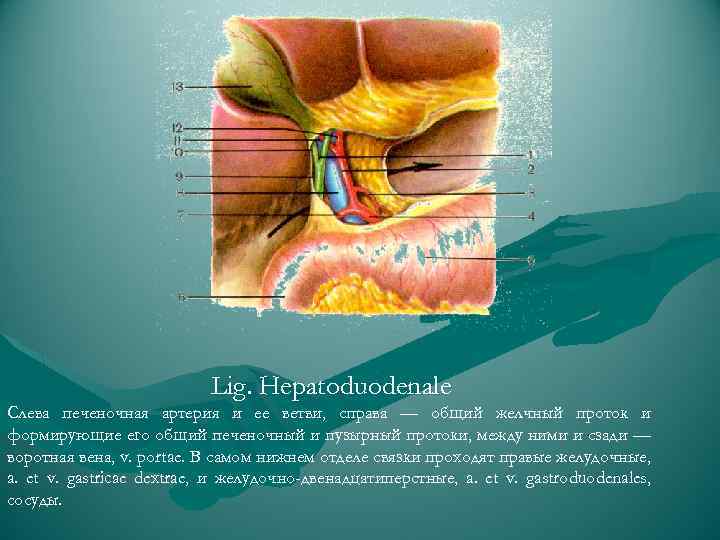

Lig. Hepatoduodenale Cлева печеночная артерия и ее ветви, справа — общий желчный проток и формирующие его общий печеночный и пузырный протоки, между ними и сзади — воротная вена, v. portae. В самом нижнем отделе связки проходят правые желудочные, a. et v. gastricae dextrae, и желудочно-двенадцатиперстные, a. et v. gastroduodenales, сосуды.

Lig. Hepatoduodenale Cлева печеночная артерия и ее ветви, справа — общий желчный проток и формирующие его общий печеночный и пузырный протоки, между ними и сзади — воротная вена, v. portae. В самом нижнем отделе связки проходят правые желудочные, a. et v. gastricae dextrae, и желудочно-двенадцатиперстные, a. et v. gastroduodenales, сосуды.